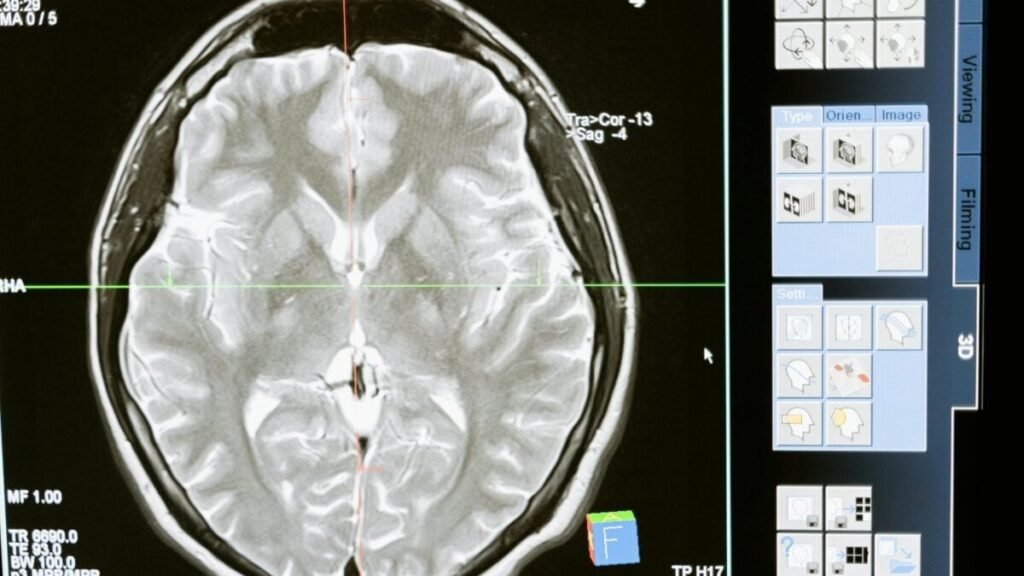

The advancement is based on implanting tiny arrays of electrodes in the motor cortex, where orders to the speech muscles originate. Even though the mouth and tongue do not move, the brain still does. Machine learning algorithms analyze these signals and reconstruct probable words from basic phonemes. Thus, a pattern corresponding to the sounds “D” and “G” can be identified as the word “dog.”